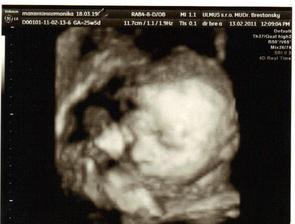

✿♥♥♥♥Bude to dievčatko!!!!! ♥♥♥♥✿

Bude to Stella 🙂

krasne 3D sono 🙂

Krasne foto dufam ze ti uz je lepsie mojko 🙂